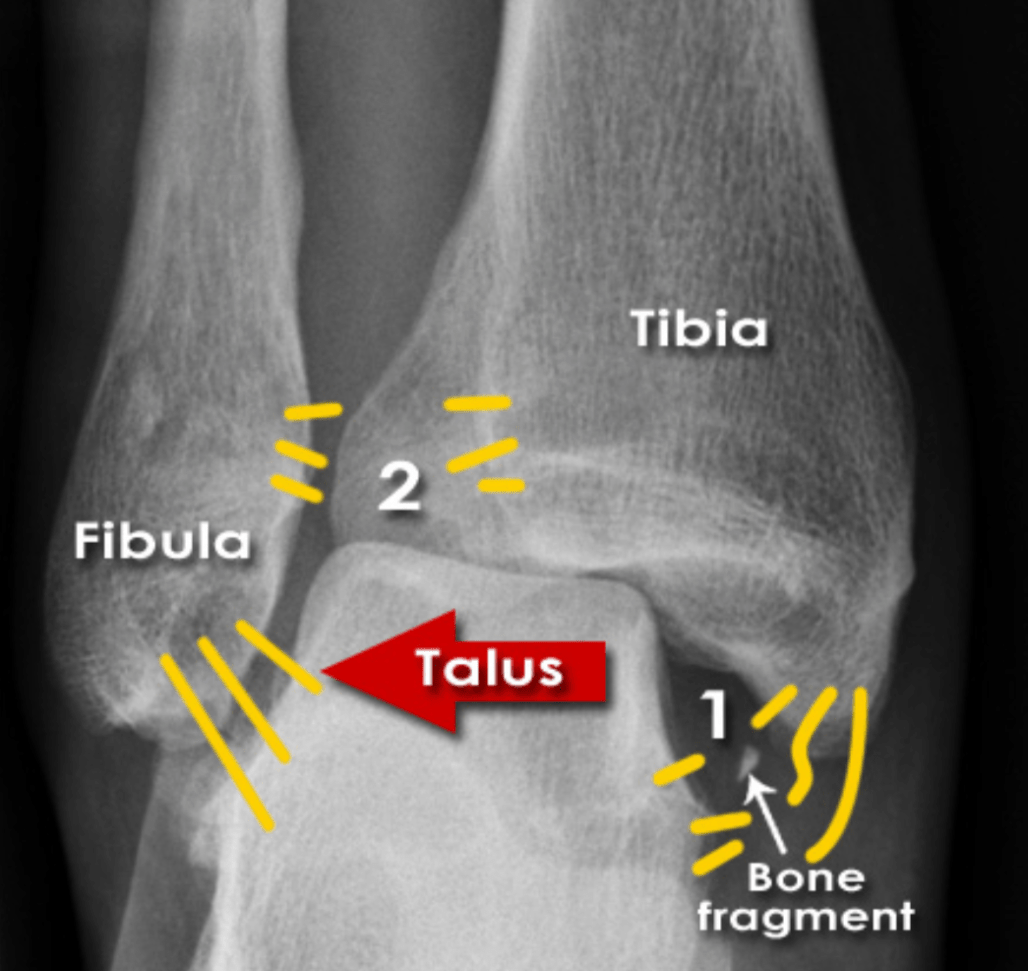

Name any abnormalities in the below imaging of ankle mortise

What is Normal?

What should you suspect if you see this image?

What is Maisonneuve Fracture?

Fracture of the proximal fibula associated with injury to the medial side of the ankle and disruption of the distal tibiofibular syndesmosis.

The medial ankle injury may be either a visible medial malleolus fracture or an invisible injury of the medial ligaments.